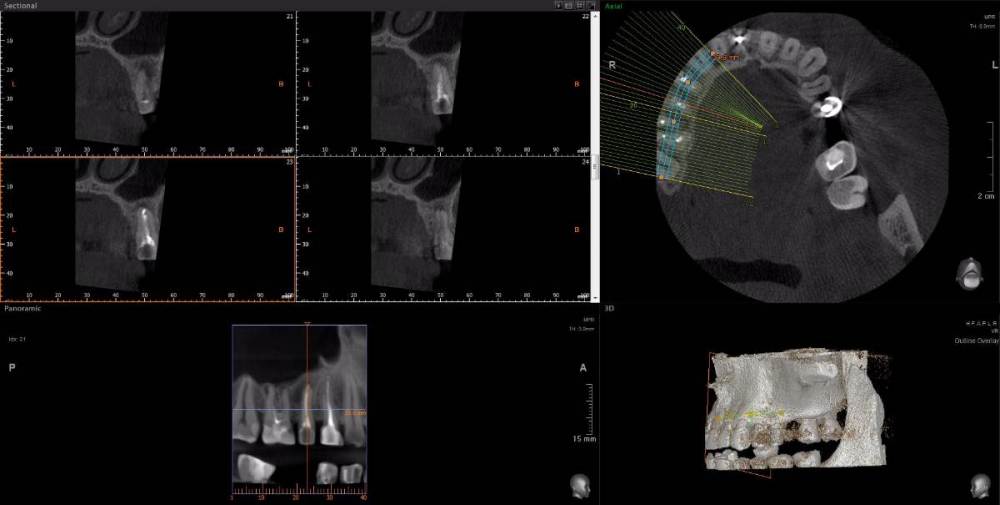

wladdX Опубликовано 15 апреля, 2021 Поделиться Опубликовано 15 апреля, 2021 Несколько скриншотов из вашей КЛКТ. Зуб 25: Зуб 27: Правая сторона: 1 Ссылка на комментарий

red_butler Опубликовано 16 апреля, 2021 Поделиться Опубликовано 16 апреля, 2021 1.5 1.6 перелечивать, 2.4 похоже кариес корня, нужно смотреть очно, 2.5 парадонтологическое поражение, смотреть очно, 2.6 ревизия корневых каналов Ссылка на комментарий